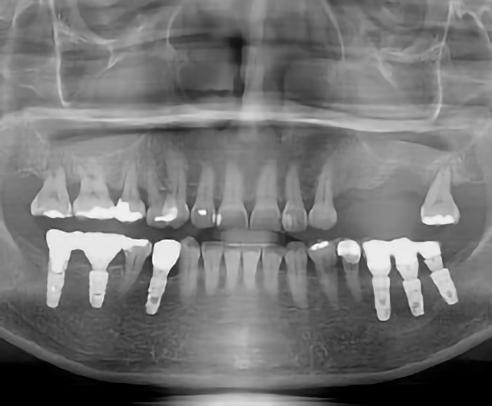

1. a–d. ábra: Műtét előtti állapot mind a négy páciensnél. 1. eset (a). 2. eset (b). 3. eset (c). 4. eset (d).

Az alábbi esettanulmányhoz négy pácienst választottunk ki (1. táblázat). Minden esetben egy, vagy több fog pótlására volt szükség, amelyhez kerámiaimplantátumokat használtunk. Valamennyi páciens általános egészségügyi állapota jó volt.

Vizsgálatok

A pótlásra szoruló fogat, vagy fogakat minden esetben legalább egy évvel a fogpótlást megelőzően eltávolítottuk. Ezen esetek egyikében sem végeztünk alveolus vagy állcsontgerinc prezervációt az eltávolítás során, illetve minden páciens jó szájhigiéniával rendelkezett. Egy kivételével minden páciensnél radiológiai analízist végeztünk CBCT-vel, amelyet

digitális implantátumtervezés követett (SICAT és Sidexis, mindkettő Dentsply Sirona; 1. ábra).